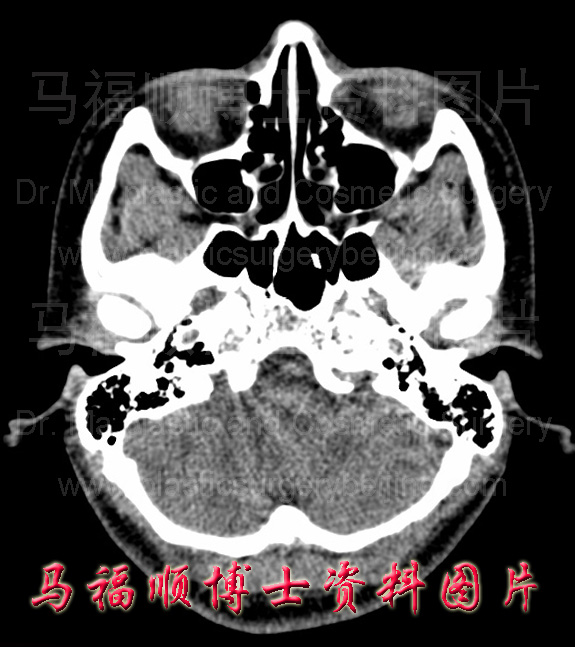

颧弓平面的面横断面图,两侧颧弓基本对称且呈弓形。

颧弓宽者的颧弓断层CT中显示颧弓的弓度大,向外侧突出明显。右侧颧弓窄者的CT断层片示颧弓的弓度小,平直。